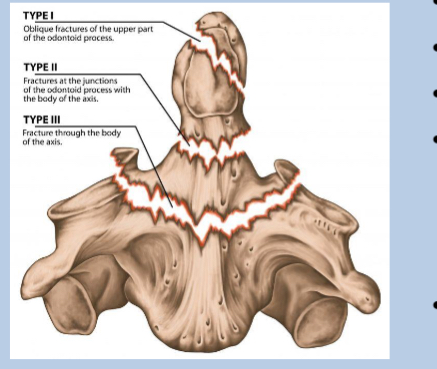

What does type 1 of odontoid peg fracture look like?

superior to the base

What does type 2 of odontoid peg fracture look like?

Transverse through the base

What does type 3 of odontoid peg fracture look like?

below base into the body